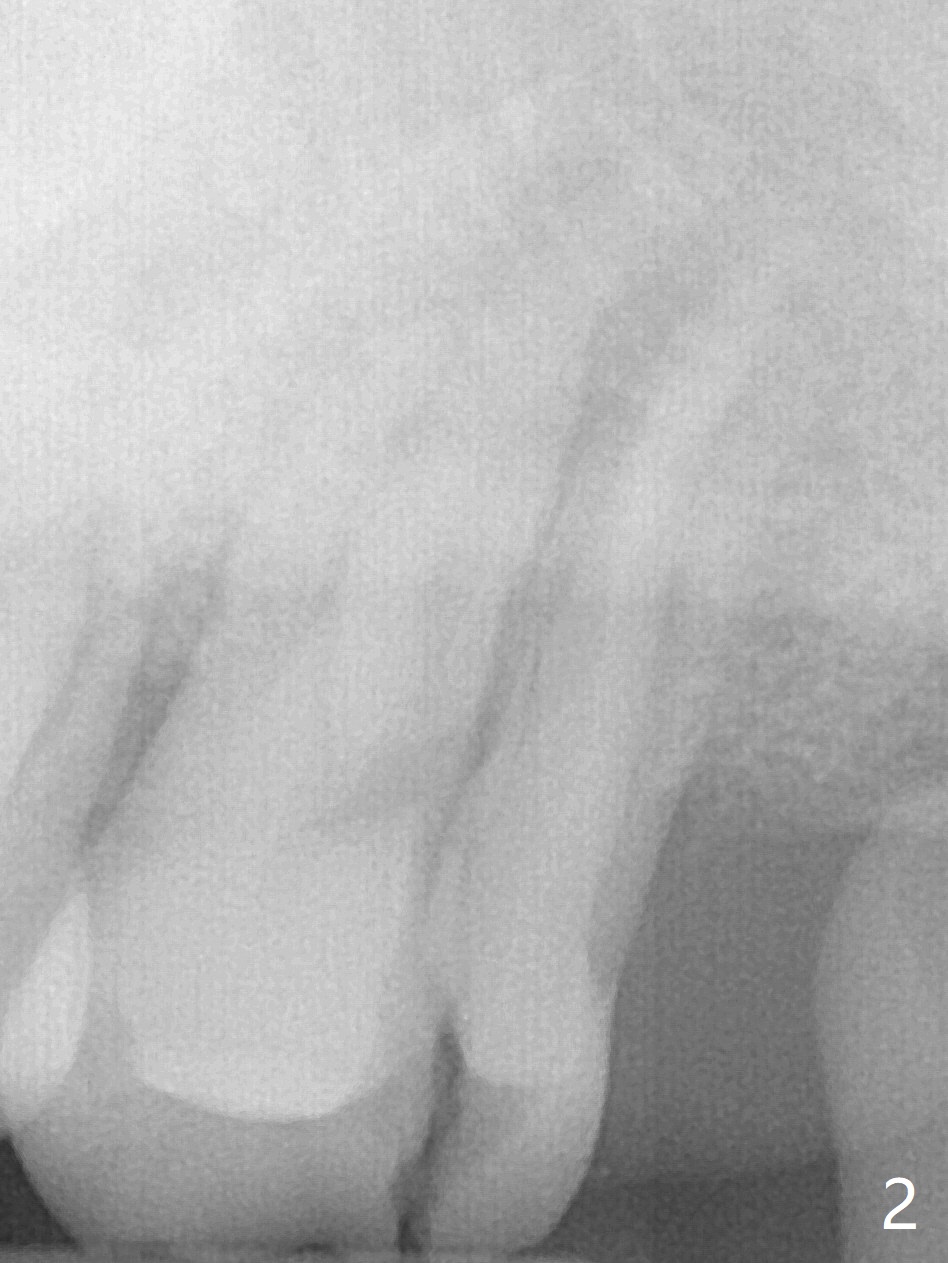

Large Upper 2nd Molar Socket After Vertical Root Split

A 45-year-old man with #4 crown fracture and C deciduous tooth returns to clinic with chief complaint of "chewing pain" UL. It seems that the distal marginal ridge of the tooth #15 has simple oblique subgingival fracture. With one carpule of Xylocaine, the distal portion cannot be removed because of pain. X-ray reveals vertical root fracture (Fig.1,2). With additional carpules of Septocaine and Marcaine, the tooth is removed. The socket is large with abundant granulation tissue. After debridement, a large amount of Vanilla graft and a whole piece of Osteogen plug is placed for socket preservation (Fig.3).